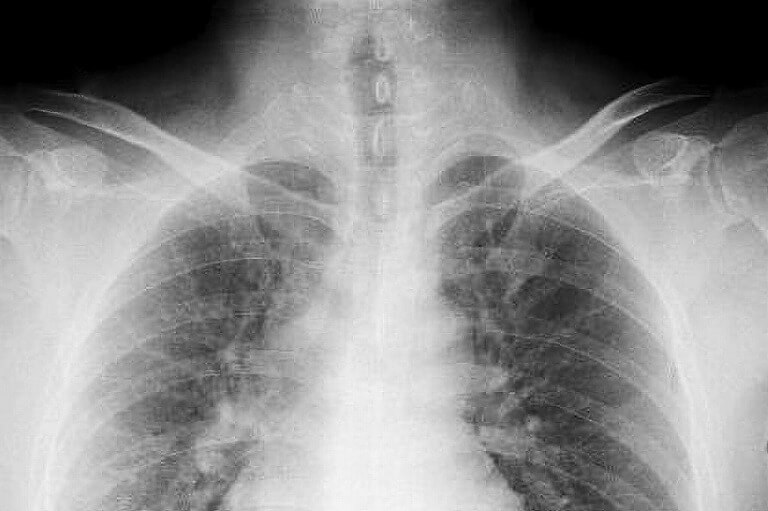

発症にはアスベスト(石綿)との関与が知られており、アスベストを吸ってから平均40年ほどとかかるとされています。日本でアスベストが輸入中止になったのは1970年代ですが、使用が全面禁止になったのは最近のことです。胸痛や咳、大量の胸水による呼吸困難・胸部圧迫感がありますが、特徴的な症状がなく早期発見が難しい病気です。そのため、過去にアスベスト曝露がある方は、定期的な胸部X線検査や胸部CT検査による検診が推奨されています。